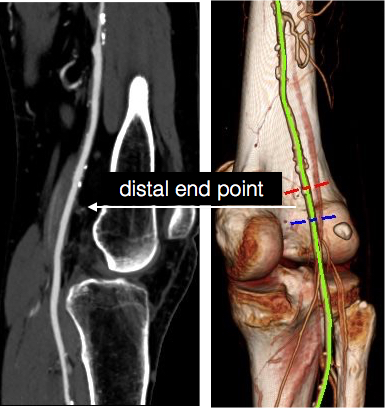

Her baseline CTA in workup of her claudication the year prior to getting stented shows the aorta and iliacs, while open, are small, with aortic lumen diameter reaching 10mm and common iliac lumen diameter at 6mm with diffuse atherosclerosis (below).

The CTA on presentation shows bilateral stent occlusion. A closer look shows the second set of stents extending the original stents both proximally into the aorta (raising the bifurcation) and distally into the external iliac and across the internal iliac origins (white arrows). The internal iliac arteries, despite the stents and on the right thrombus in the stent, supply flow to the external iliac arteries which have not thrombosed.

A postoperative CTA showed wide patency of the restored aorta and iliac arteries.